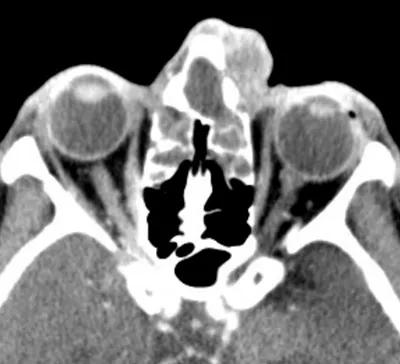

Image C: CT showing dense opacification of frontal sinus with anterior table erosion.

CT imaging revealed a destructive infection within the frontal sinus, causing some erosion of the anterior table. The abscess extended along the inferior portion of the frontal sinus (Image C). Pott’s puffy tumor typically manifests with swelling on the forehead associated with the frontal sinusitis and subperiosteal abscess. However, the patient’s symptoms and the CT imaging confirmed Dr. Perry’s theory that she had a rare presentation of Pott’s puffy tumor.